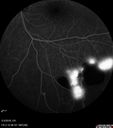

51 year old male with a broken vein in the left eye. His vision is pretty good. He has not noticed any vision change. You asked him to come here for further evaluation in the left eye. VA OD: sc20/63 PH20/25-2 NccJ1 VA OS: sc20/20 Patient had scatter laser to non-perfused retina and never had a vitreous hemorrhage (yet)

Coats' Disease -51 year old asymptomatic male450 views20/20 vision - had laser to non-perfusion because of proliferation.00000